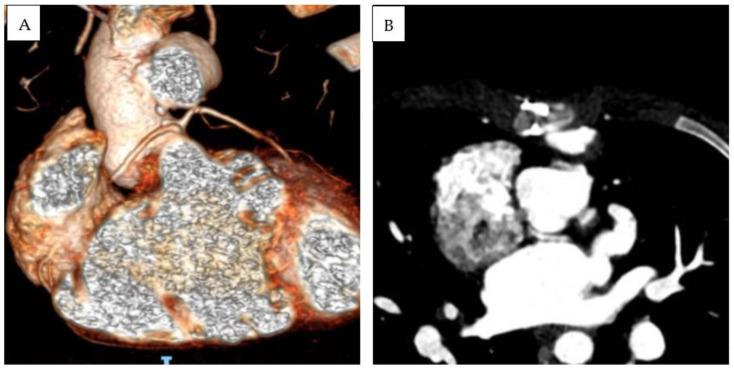

Double-outlet left ventricle (DOLV) is an abnormal ventriculo-arterial connection characterized by the origin of both great arteries from the morphological left ventricle. The aim of our paper is to describe the morphological and imaging features of DOLV and to assess the prevalence of the associated malformations and their surgical outcomes. METHODS From 2011 to 2022, we retrospectively reviewed the electronic case records of patients diagnosed with DOLV at the Bambino Gesu Children's Hospital. A systematic search was developed in MEDLINE, Web of Science, and EMBASE databases to identify reports assessing the morphology and outcomes of DOLV between 1975 and 2023. RESULTS: Over a median follow-up of 9.9 years (IQR 7.8-11.7 y), four cases of DOLV were identified at our institution. Two patients were diagnosed with (S,D,D) DOLV subaortic VSD and pulmonary stenosis (PS): one patient had (S,D,D) DOLV with doubly committed VSD and hypoplastic right ventricle, and another patient had (S,D,L) DOLV with subaortic VSD and PS (malposition type). Pulmonary stenosis was the most commonly associated lesion (75%). LITERATURE REVIEW: After systematic evaluation, a total of 12 reports fulfilled the eligibility criteria and were included in our analysis. PS or right ventricular outflow tract obstruction was the most commonly associated lesion (69%, 95% CI 62-76%). The most common locations of VSD were subaortic (pooled prevalence: 75%, 95% CI 68-81), subpulmonary (15%, 95% CI 10-21), and doubly committed (7%, 95% CI 4-12). The position of the great arteries showed that d-transposition of the aorta was present in 128 cases (59% 95% CI 42-74), and l-transposition was present in 77 cases (35%, 95% CI 29-43).

双出口左心室(DOLV)是一种异常的心室-动脉连接,其特征为两大动脉均起源于形态学上的左心室。本文的目的是描述双出口左心室的形态学和影像学特征,并评估相关畸形的患病率及其手术结果。方法:2011年至2022年,我们回顾性分析了在 Bambino Gesu儿童医院诊断为双出口左心室的患者的电子病历。在 MEDLINE、科学网和 EMBASE数据库中进行了系统检索,以识别 1975年至 2023年期间评估双出口左心室形态学和结果的报告。结果:在中位随访 9.9年(四分位间距 7.8 - 11.7年)期间,我们机构共识别出 4例双出口左心室患者。2例患者被诊断为(S,D,D)型双出口左心室合并主动脉下室间隔缺损和肺动脉狭窄(PS):1例患者为(S,D,D)型双出口左心室合并双室连接室间隔缺损和右心室发育不良,另 1例患者为(S,D,L)型双出口左心室合并主动脉下室间隔缺损和 PS(位置异常型)。肺动脉狭窄是最常见的相关病变(75%)。文献综述:经过系统评估,共有 12篇报告符合纳入标准并纳入我们的分析。肺动脉狭窄或右心室流出道梗阻是最常见的相关病变(69%,95%CI 62 - 76%)。室间隔缺损最常见的位置是主动脉下(合并患病率:75%,95%CI 68 - 81)、肺动脉下(15%,95%CI 10 - 21)和双室连接(7%,95%CI 4 - 12)。大动脉的位置显示,128例(59%,95%CI 42 - 74)存在主动脉 d-转位,77例(35%,95%CI 29 - 43)存在 l-转位。